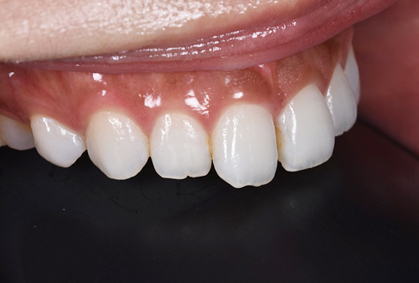

初診時

患者様の主訴は、「前歯の隙間が気になる」

でした。

矯正治療をおすすめしましたが、矯正治療の期間が長いということでセラミック治療を選択することになりました。写真をみるとすきっ歯も気になりますが、以前に詰めたプラスティックも変色して着色しており気になります。

仮歯

セラミックの前に仮歯を調整している段階になります。できればということで歯の長さも短くしたいというリクエストがありましたので、仮歯で調整をしながら様子を見ました。

歯の長さを短くする際に歯を削りますので神経の治療が必要になることがありますので、しみたり・噛んで痛くないか?を約1ヶ月様子を見ました。色・形など仮歯でほぼ問題ないということでしたので、最終的な型採りをしました。

セラミックセット

最終的なジルコニアボンドクラウンをセットしました。すきっ歯がまずなくなりました。また、長かった歯が短くなりましたので本人の希望に沿うことができました。